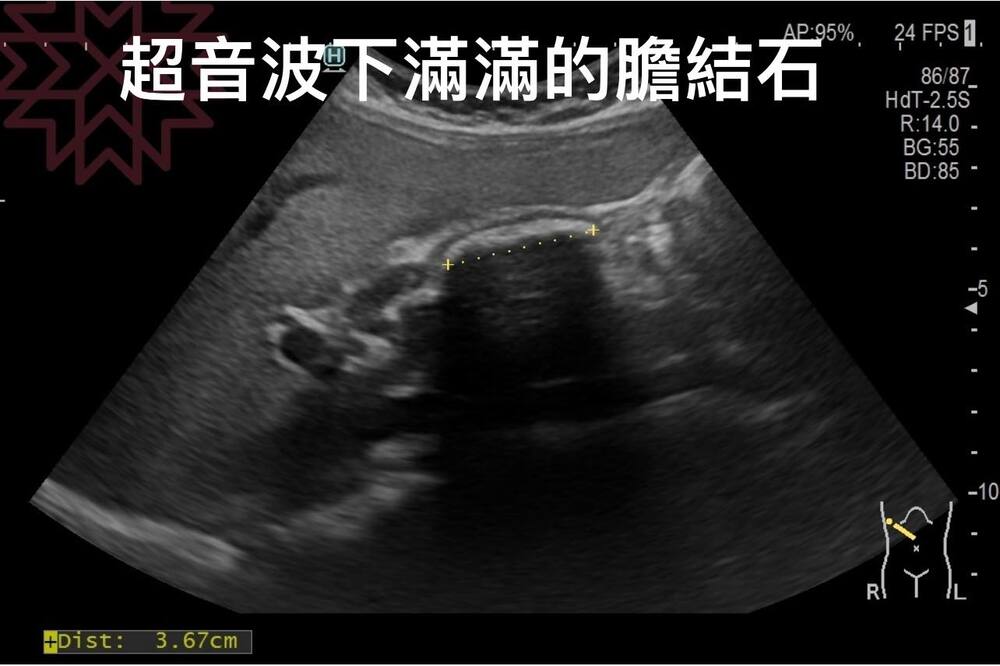

胃痛復發竟發現「314顆」膽結石! 尿尿這顏色藏警訊 醫提4點好發情況

當胃痛找上門時,有不少人會選擇到藥局買胃藥,緩解疼痛感,不過日前就有一名孕婦患者胃痛的症狀時常復發,平時都是吃止痛藥緩解,經檢查後才發現,原來是因為膽囊裡面佈滿314顆結石,於是進行手術取出。對此,醫師林相宏也提醒民眾,有4種狀況容易引發膽結石。

檢查結果顯示,患者的胃鏡及大腸鏡都非常正常,但膽囊卻有滿滿的結石,膽壁還增厚,安排手術取出後,順利解決患者的胃痛、脹氣、肚子痛的毛病。林相宏還表示,患者在住院期間因為無聊,開始計算取出的石頭,沒想到竟有「314顆」,讓他相當傻眼。